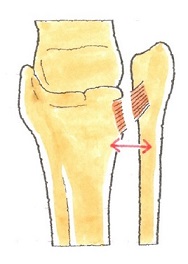

そのときは、脛骨の骨切りを行って傾きを矯正します。「下位脛骨骨切り術」といいます。

(上の図)下位脛骨骨切り術

脛骨の足首に近い部分で骨の向きを変えて、より軟骨が残っている部分に体重がかかる軸を移動させるものです。

これによって、軟骨が消失して狭くなった関節が開き、軟骨組織が再生することを促します。